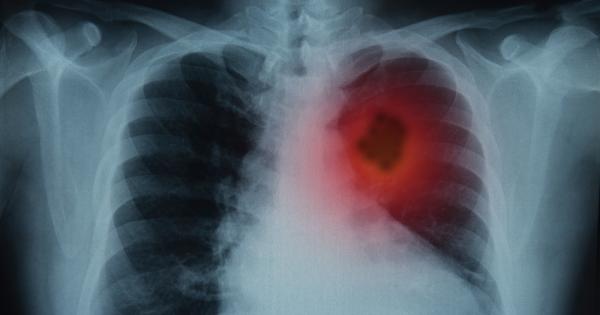

Ракът на белия дроб е сред петте най често срещани видове рак